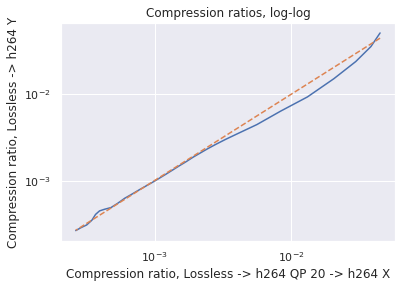

Data: As in [9], our colonoscopy video dataset was collected from screening colonoscopy procedures performed in three hospitals. We used a detector trained on a 16K video subset of the dataset, and we computed our classical codec analyses on a different 80 video subset (2.2M frames, 15K polyp frames). All videos and metadata were deidentified according to the Health Insurance Portability and Accountability Act Safe Harbor. Ground truth polyp labeling was provided by the gastroenterologist annotators described in [9]. The annotators were paid on an hourly basis, and pay was not based on the results they provided. The videos were compressed using H264 QP20 when transmitted from the hospitals. To justify our analyzing already-compressed videos, we used a small number of lossless videos to investigate the impact of re-compressing compressed videos to QP (so called “generation loss"). We found that the impact was negligible (see Appendix for details).

Since our dataset was compressed to be transferred from hospitals, we first investigated the impact of multiple stages of compression ("generation loss"). We used lossless video (24 seconds, 1.4GB) collected from an endoscope viewing dyed, non-human tissue. This gave the video the motion and texture characteristics of a colonoscopy. We then compared video quality between two compression schemes: compressing using H264 QP , where , and compressing to H264 QP20, then to H264 QP (when referring explicitly to this comparison, we will concisely refer to the latter as ’QP’). We then compared the average frame quality between these two schemes using two quality metrics (see ’Metrics’ section). The quality differences between these two compression schemes was minor in terms of PSNR-CbCr, which justifies our working with video data already compressed by H264 QP20.